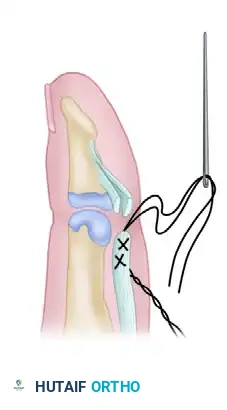

Figure 3: The completed Wagner technique of profundus advancement, showing the tendon secured into the distal phalanx and tied over a dorsal pull-out button.